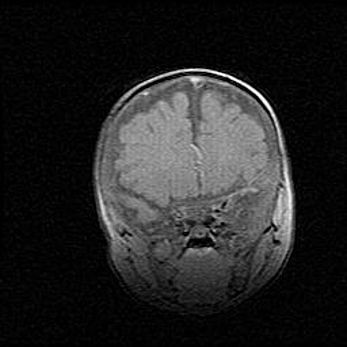

Церебральная ишемия II.

Возраст: 5 дней

Вес: 3400 г

Пол: женский

Окружность головы: 35 см

Срок гестации: 39 недель

Церебральная ишемия – это заболевание, характеризующееся недостаточностью (гипоксией) либо полным прекращением (аноксией) снабжения мозга кислородом по причине закупорки одного или нескольких сосудов. Это приводит к  что метаболическим расстройствам различной степени тяжести в тканях головного мозга, развитию коагуляционных некрозов и гибели нейронов.